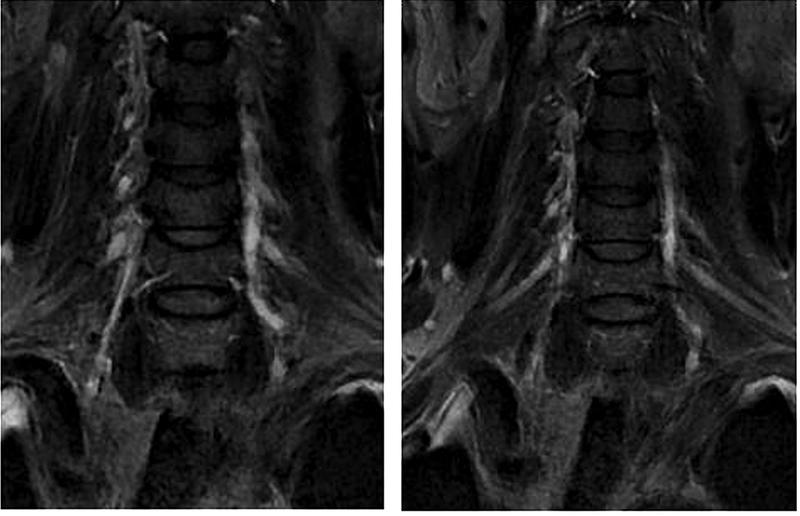

神经内科张桂莲教授带领的介入团队在影像科李晓会教授团队的鼎力支持下,反复查阅相关文献,尝试多种新型磁共振成像技术,最终历时4个小时,克服了肺内气体对磁共振成像质量的影响,通过特殊的MRI成像技术及体表定位技术,清晰显示出脑血管造影及高分辨核磁共振不能显示的闭塞的椎动脉开口,使之前无法完成的高难度手术变成可能。

最终,在患者入院第4天,张桂莲教授带领的介入团队选择局麻条件下为患者成功实施了神经介入领域的高难度手术—左侧无残端椎动脉长节段慢性闭塞再通术。因术前清晰的影像显影及准确的体外定位标记,左侧优势椎动脉顺利开通,手术耗时仅仅约90分钟。术中及术后患者配合良好,无任何不适。出院前复查头颈一体化超声提示左侧椎动脉支架位置良好,血流通畅,颅内血流速度及频谱未见明显异常。充分向患者及家属告知出院注意事项及复查时间后,目前该患者已顺利出院。